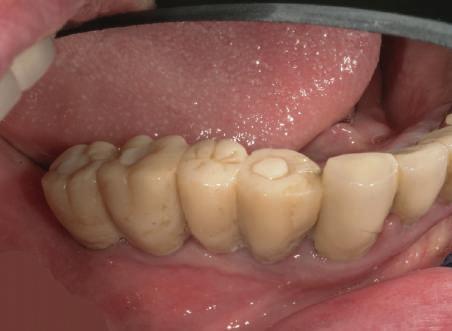

Reprepararea intraorală a bonturilor Acest pacient prezenta dentiţia maxilară compromisă, refuzând proteza mobilizabilă. Prin abordarea în etape, se menţin o parte din bonturile dentare naturale; s-a observat recesie în momentul amprentării pentru cel de-al doilea grup de implanturi.

Fig. 1 prezintă pacientul după inserarea primului set de bonturi implantare individualizate; dinţii naturali adiacenţi

sunt încă prezenţi pentru a susţine puntea provizorie.

Şapte luni mai târziu (fig. 2), acele bonturi individualizate din prima etapă au manifestat semne de recesie de 1-3mm. Atitudine: S-a decis reprepararea intraorală a tuturor bonturilor (fig. 3), astfel încât toate marginile bonturilor să fie la nivelul sau sub marginea gingivală (de notat că 1.1. şi 2.1. au fost submersaţi ulterior pentru a avea sprijin implantar deplin).

Deşi reprepararea a îmbunătăţit marcat estetica finală, a necesitat aplicarea şnurului de retracţie, amprente noi şi turnări noi.

Un caz separat dar similar ilustrează în figurile 4 și 5 reprepararea intraorală a bontului.

Cazul (1): Reprepararea intraorală a bonturilor Figurile

1. Aspect după inserarea primului set de bonturi implantare individualizate.

2. După 7 luni, bonturile individualizate din prima etapă au prezentat recesie de 1-3mm.

3. Bonturile repreparate intraoral.

Alt caz (1) Figurile

4. După osteointegrarea implantului 2.4., s-a observat recesia în etapa de amprentare a implantului 2.5.; s-a decis reprepararea marginilor bontului individualizat CAD/CAM 2.4. Înainte de preparare s-a aplicat şnur de retracţie pentru a evita lezarea ţesutului şi a îmbunătăţi vizibilitatea dintelui 2.3. şi a marginii bontului implantar individualizat. Aşa cum era de aşteptat, recesia a fost mai mare de-a lungul versantului distal al bontului 2.4. adiacent locului de extracţie vindecat/cu implantul mai nou.

5. Bontul individualizat aplicat (2.5.) cu bontul repreparat anterior (2.4.). Nu a survenit recesie nouă de o perioadă de peste 3 ani.